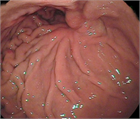

1. 難渋例の症例について画像を用いて解説した。